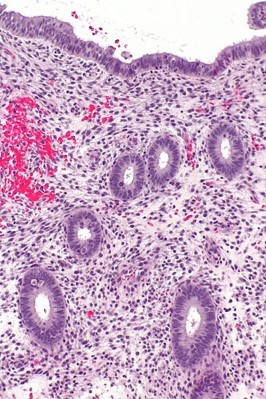

Appreciate this pic of normal endometrium